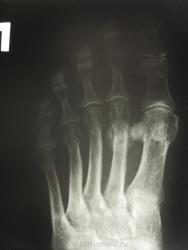

женщина обратилась с жалобами к участковому терапевту на боли во 2 и 3 пальцах правой стопы, предварительный диагноз у них как всегда " артроз", про травму ничего не пишут в амбулаторной карте, как внешне выглядит стопа тоже не описывают. Может ли это быть патологическим переломом????

Перелом по типу маршевого, но так как на фоне минералопении - это ближе к Лоозера, чем Дойчлендера...

Патологическая перестройка от перенапряжения может возникать в разных костях, однако наиболее типичные места – дистальный отдел 2-й или 3-й (реже) плюсневых костей и проксимальный метафиз большой берцовой кости. Первая локализация носит название в литературе как «маршевая стопа», перелом Дойчлендера, усталостная стопа и др. и встречается чаще у солдат-новобранцев. Перестройка большой берцовой кости встречается чаще у спортсменов в период интенсивных тренировок.

На рентгенограммах выявляется локальная периостальная реакция в виде одно- или многослойного периостоза. Соответственно ему в костномозговом канале появляется склероз, сужающий просвет канала. В кортикальном слое и среди склероза видна полоска просветления, чаще имеющая клиновидную форму- собственно « ползучий » перелом. При продолжении действии нагрузки он постепенно увеличивается. Однако если травмирующий фактор прекращает свое действие, достаточно быстро восстанавливается нормальная структура кости.